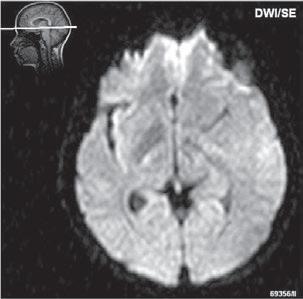

Roztroušená skleróza (RS) 189

Neuromyelitis optica (NMO) – Devicova nemoc 196

Akutní diseminovaná encefalomyelitida (ADEM) 199

Progresivní multifokální leukoencefalopatie (PML)